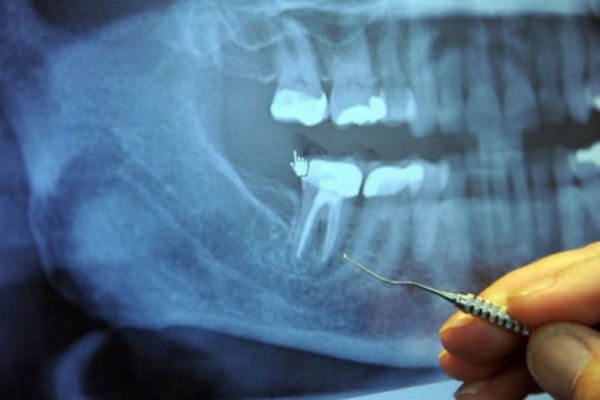

U sredini svakog zuba nalazi se zubna šupljina i u njoj pulpa, koja povezuje krvne sudove i nerve. Oko zubne šupljine se nalazi dentin, koji je sačinjen od živih ćelija koje luče tvrdu mineralnu supstancu. Spoljašnji dio zuba naziva se enamel i on okružuje dentin.

Korijeni svakog zuba dopiru do vilice i ostaju na svom mjestu zahvaljujući peridontalnom ligamentu. Stomatologe u školi uče da svaki zub ima 1-4 veća kanala. Međutim, postoji gomila kanala koja se uopšte ne pominje.

Svaki zub ima čitav lavirint sitnih cjevčica koje bi, kad bi se razmotale, bile dužine oko nekoliko kilometara. Veston Prajs je identifikovao 75 odvojenih pristupnih kanala u jednom centralnom sjekutiću.

Kad zubar izvede operaciju vađenja živaca, on probuši zub, a zatim ispuni šupljinu supstancom koja odsijeca dotok krvi do zuba, tako da ona više ne može da cirkuliše kroz zub. Međutim, lavirint cijevčica i dalje ostaje tamo, a bakterije, koje više nemaju svoj izvor hrane, kriju se u ovim tunelima gdje su bezbjedne od antibiotika i imune odbrane organizma.